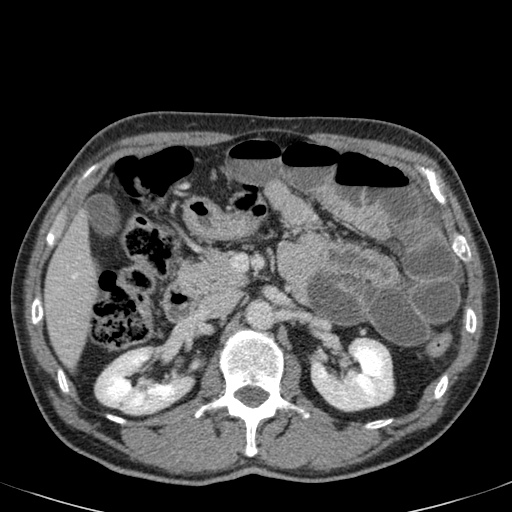

Nếu quai kín dài hơn và định hướng vuông góc với mặt phẳng cắt, chúng ta sẽ thấy một cụm quai ruột như trong ca lâm sàng bên trái.

Đôi khi điều này khó nhận biết chỉ trên các lát cắt ngang và các tái tạo mặt phẳng coronal hoặc sagittal có thể hữu ích.

Trong ca này, cũng có phù nề mạc treo và cổ